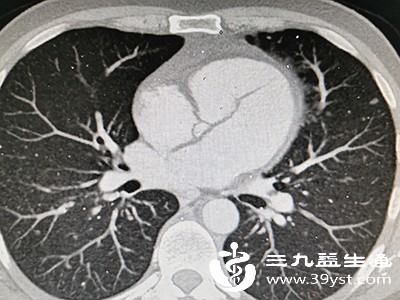

不同的影像学检查技术和设备分辨率不同,可能会对肺部纹理的显示产生影响。例如,胸部X线检查与胸部CT检查相比,CT分辨率更高,能更清晰地显示肺部纹理,有时可能会出现X线未发现异常而CT提示纹理增多增粗的情况。此外,检查时的投照条件、患者的呼吸状态等也可能影响结果,如吸气不足时,肺部膨胀不够,纹理会显得相对密集。